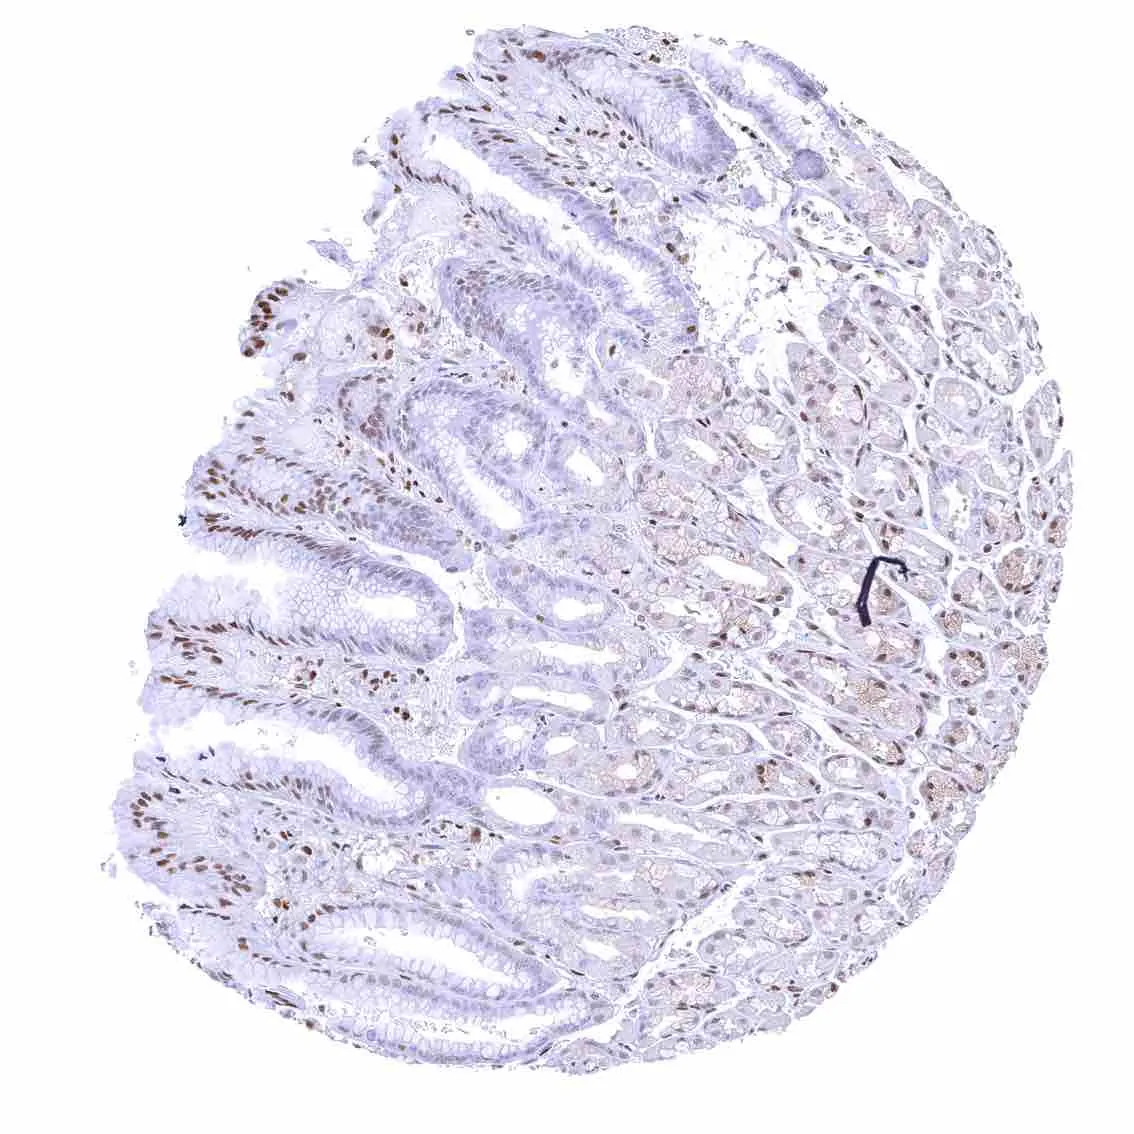

Colon descendens, mucosa

Colon descendens, muscular wall – Strong nuclear p27 staining of most smooth muscle and neuronal cells.